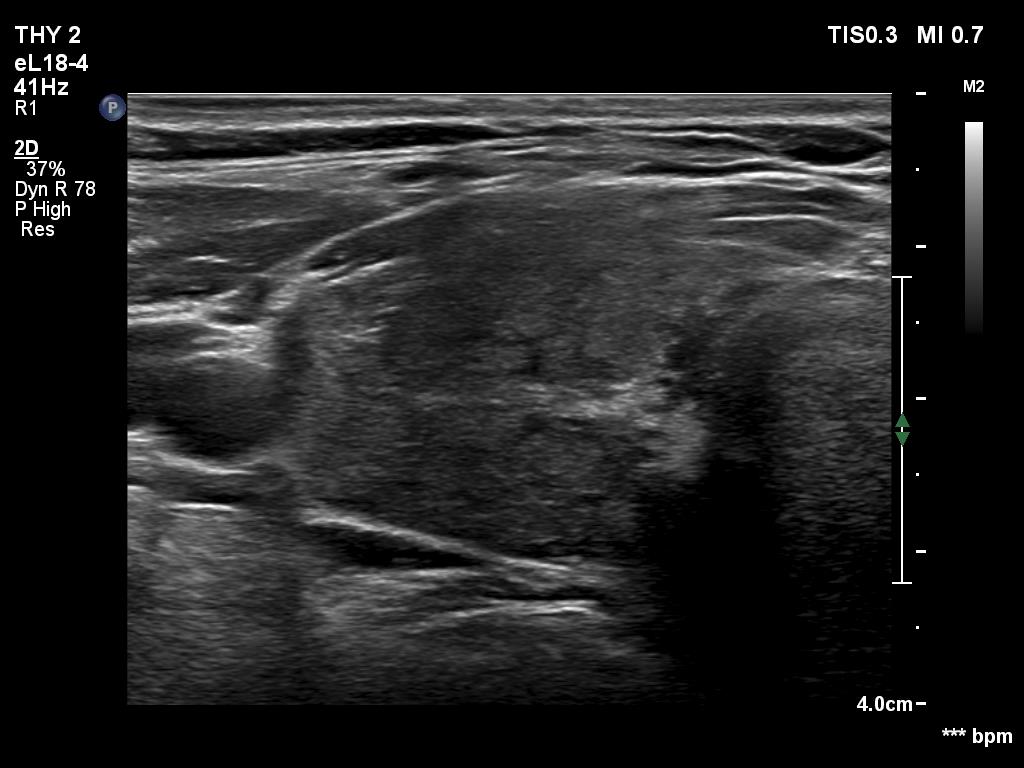

Second examination seven years later (ultrasonographic picture 1)

Right lobe, longitudinal scan